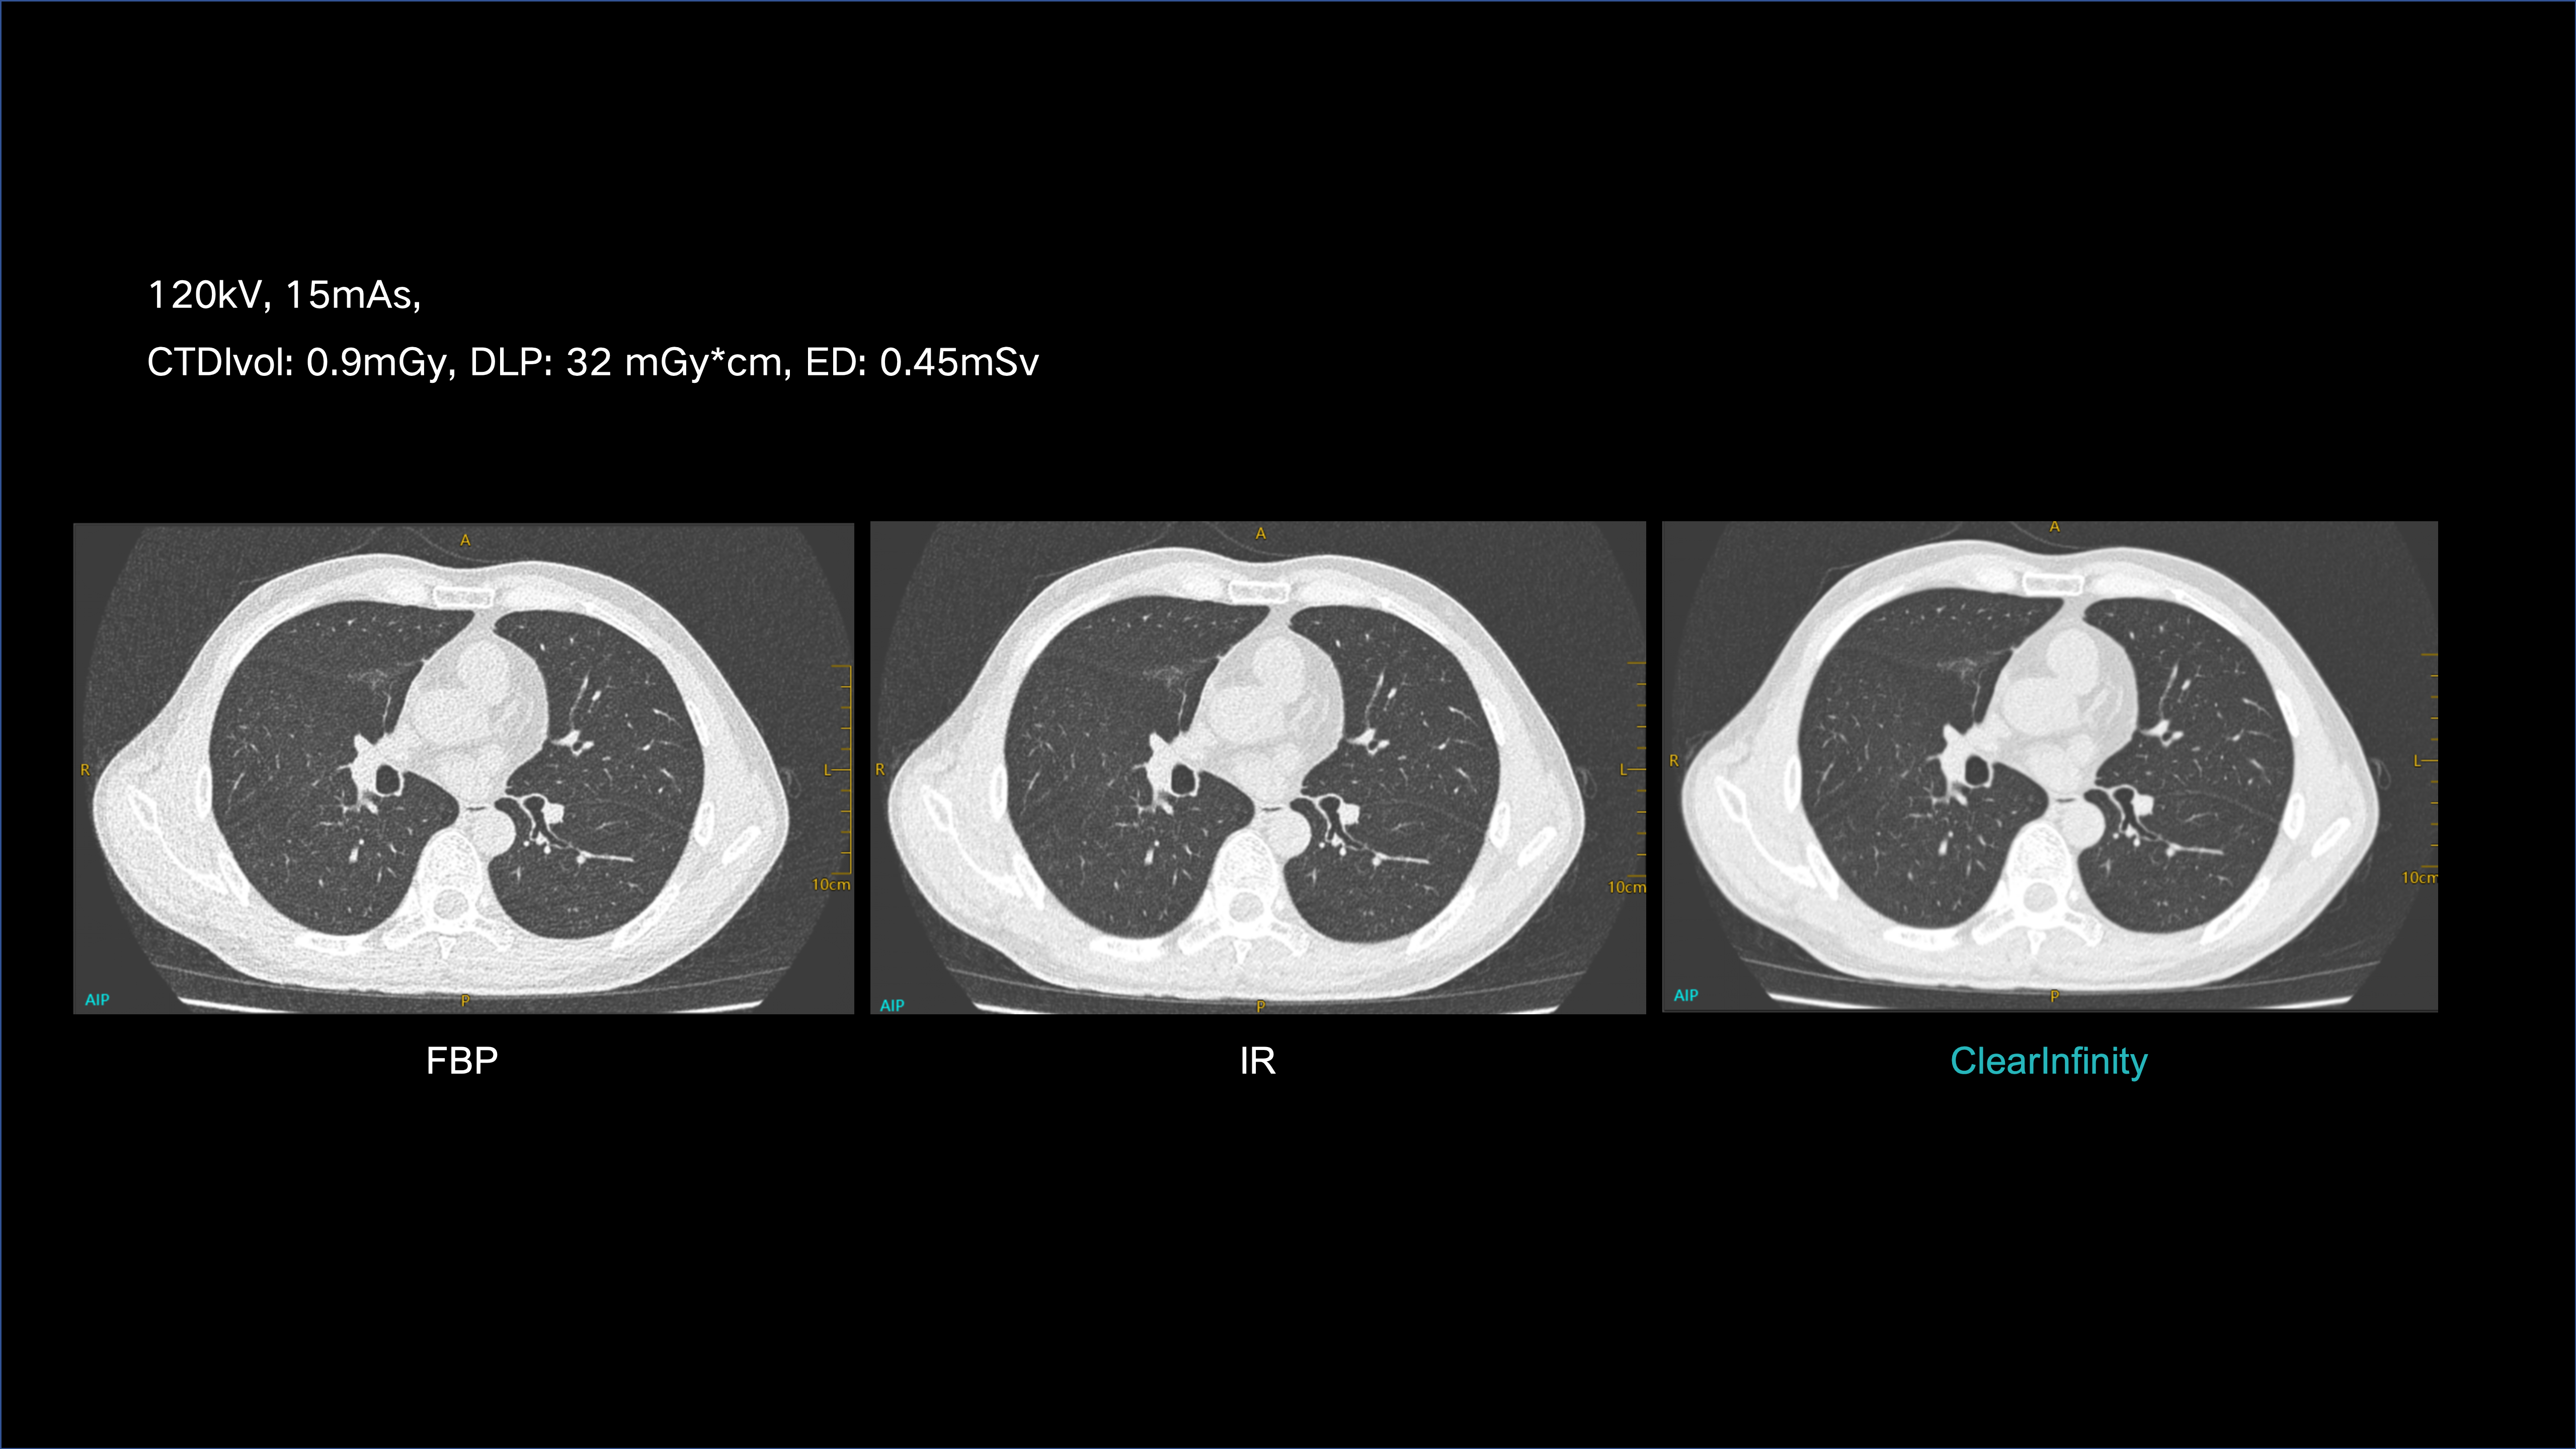

ClearInfinity AI preserves natural texture while ensuring ultra-low-dose clarity.

Delivers extraordinary spatial detail for confident, accurate diagnosis.